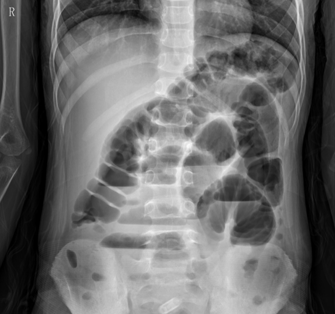

立位腹部X線平片如下圖。

(4)立位腹部X線平片可見多個(gè)氣液平面。(1分)